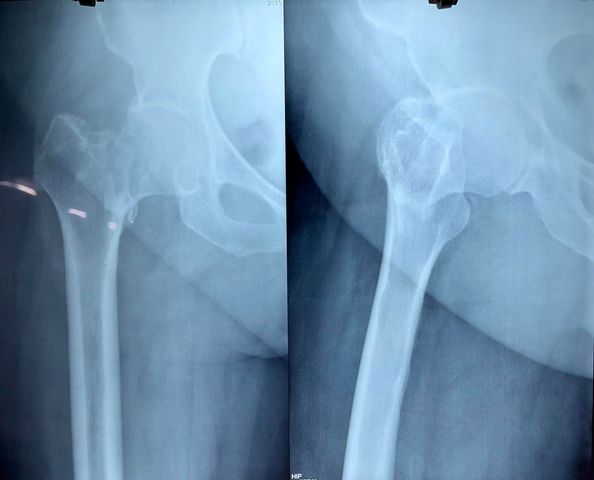

This is one of my early IPGMER days total knee replacement (tkr) surgery done on the right knee for grade 4 osteoarthrosis with medial tibial deficiency that was counteracted with bone graft held with screws. This post would be incomplete without gratitude to Dr. Debasis Mukherjee and Dr. @Chetan Chetan